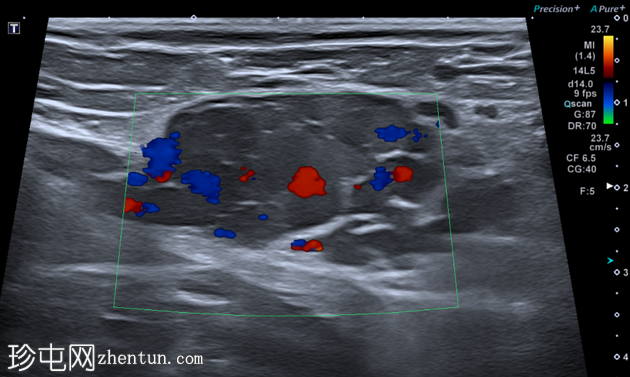

横切面

虽然本次图像未达到最佳效果,但彩色多普勒显示内部血流信号增强,Valsalva动作后血流信号增加,证实该结构为静脉性质。

未见淋巴结肿大。